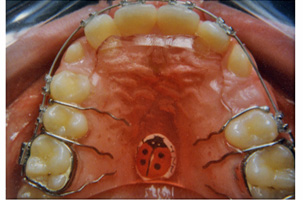

Ακίνητοι Μηχανισμοί - Ορθοδοντικός Δρ. Ζαρμπή

Πρόκειται για μηχανισμούς που συγκολλούνται στα δόντια και δε μπορούν να αφαιρεθούν από τον ασθενή. Απευθύνονται σε μετακινήσεις ακριβείας μεμονωμένων δοντιών κατά μήκος του άνω ή κάτω οδοντικού τόξου, ή οδοντικών ομάδων μεταξύ τους.

Αποτελούνται από πολλά διαφορετικά τμήματα που λειτουργούν ως ένα σύστημα το οποίο με περιοδικές ρυθμίσεις επιτυγχάνει τις επιθυμητές οδοντικές μετακινήσεις. Ακολουθεί ανάλυση των τμημάτων των ακίνητων μηχανισμών:

ΔΑΚΤΥΛΙΟΙ: Οι δακτύλιοι είναι μεταλλικά δακτυλίδια που μπαίνουν στα πίσω δόντια. Οι δακτύλιοι συγκολλούνται στο δόντι με τη βοήθεια μιας ειδικής κόλλας που περιέχει φθόριο ώστε να αποφευχθεί τυχούσα απασβεστίωση κατά τη διάρκεια της θεραπείας. Η συγκόλληση αυτή έχει μεγάλη αντοχή κι αντέχει στις δυνάμεις της μάσησης.

ΑΓΚΙΣΤΡΑ: Εκείνα τα κομμάτια του μηχανισμού που συγκρατούν το τόξο σε κάθε δόντι. Το τόξο μπαίνει σε μια εσοχή του άγκιστρου. Τα άγκιστρα κολλούνται απευθείας πάνω στα δόντια. Τα άγκιστρα είναι μεταλλικά ή κεραμικά. Καθώς  συγκολλούνται πάνω στην αδαμαντίνη τα άγκιστρα είναι πιο ευαίσθητα στο να ξεκολλήσουν από ό, τι οι δακτύλιοι.

ΤΟΞΟ (ΤΟΞΑ): Τα βασικά σύρματα ή τόξα παίρνουν ειδικό σχήμα ώστε να ταιριάζουν γύρω από τα δόντια και να μπαίνουν στις ειδικές εσοχές στα άγκιστρα. Τα τόξα συγκρατούνται στη θέση τους από μια σειρά μικρών λαστιχένιων δακτυλιδιών (λαστιχάκια) που κρατούν το τόξο μέσα στα άγκιστρα. Τα δόντια μετακινούνται λόγω των δυνάμεων που ασκούνται πάνω τους από τα τόξα. Οι δυνάμεις αυτές πάλι δημιουργούνται από τον ορθοδοντικό μέσω των καμπυλών και των γωνιών που έχει κάνει εκείνος στο τόξο έτσι ωστέ αυτό να οδηγεί την μετακίνηση των δοντιών. ΟΠΟΙΑΔΗΠΟΤΕ ΕΠΙΠΡΟΣΘΕΤΗ  ΚΑΜΠΥΛΗ Ή ΓΩΝΙΑ ΣΤΟ ΤΟΞΟ ΠΟΥ ΠΡΟΚΛΗΘΗΚΕ ΑΠΟ ΣΚΛΗΡΗ ΤΡΟΦΗ Ή ΧΤΥΠΗΜΑ ΜΠΟΡΕΙ ΝΑ ΜΕΤΑΚΙΝΗΣΕΙ ΤΑ ΔΟΝΤΙΑ ΣΕ ΜΗ ΕΠΙΘΥΜΗΤΗ ΘΕΣΗ.